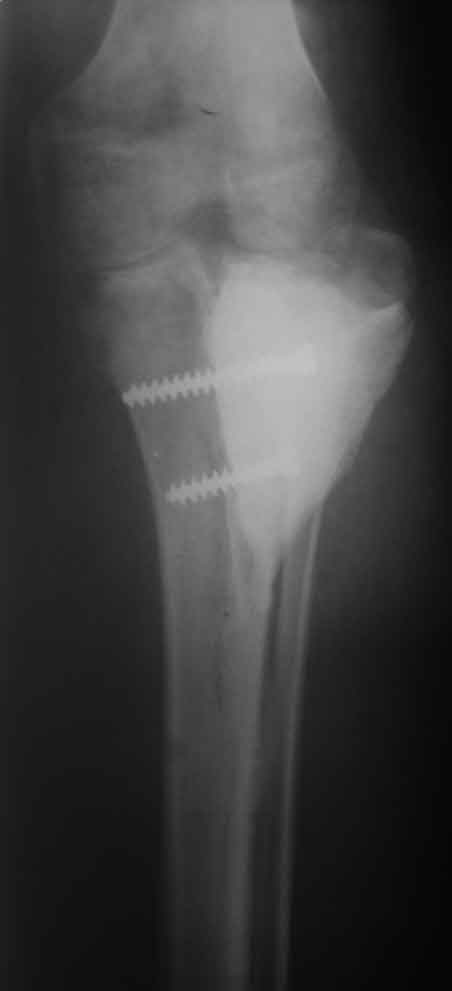

[Ortho] Костный и мягкотканный дефект голени

Рентген, интраоперационные фото и после снятия повязки